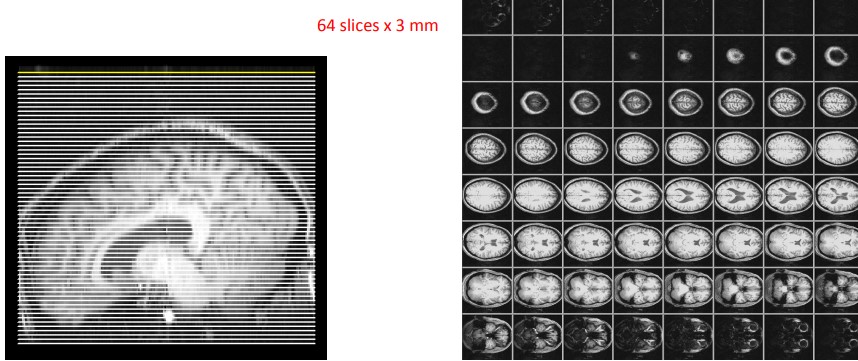

Figure 14.11: Stage 2 Anatomical Image Acquisition

The images here are related to neuronal activity and are usually low-resolution images. All slices at a single time lead to a volume.